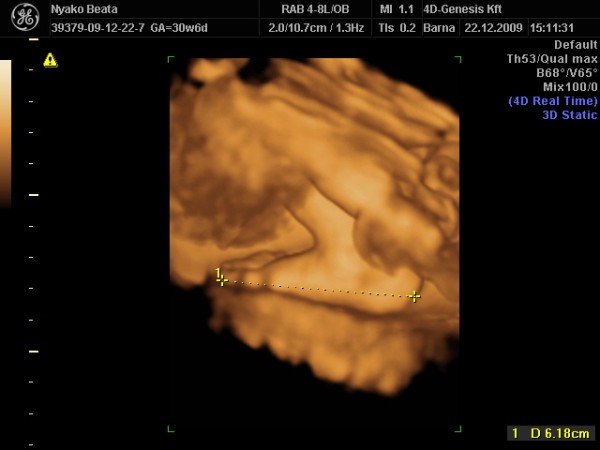

Voltunk 4D-n!

A jo hir az, hogy Erikkel minden rendben. Nem lesz oriasi baba ugy nez ki, de nem is tunik kicsinek. A feje nagyobb joval, mint kellene (meg sem lepodom), a pocakkorfogat par nappal kisebb, a tobbi merete picivel nagyobb, vagy epp kornak megfelelo. Atlagban azt dobta a gep, hogy 5 nappal idosebb a terhesseg.

A sulya 1600 gramm. Fejjel lefele van.

Hatarozottan fiu, konkretan lattuk a futyi tovet es a komplett zacsit. Meg kozepvonal is kiveheto volt rajta. Szep nagy feszes csomag.

A placenta nem szetterulo, hanem egy nagy kupacban van, vastag. Bujt is moge a gyerek szinte vegig, konkretan belenyomta a fejet es nyalogatta, ugyhogy az arcfotokkal jo sokat szenvedett a szonografus, de megoldotta.

A placenta egyebkent tokeletesen megfelel a terhessegi kornak, nem tul meszes, egy-ket potty mar van rajta, de allitolag ez mar normalis.

Mondtam, hogy a doki kicsinek talalta a mehemet es feltehetoen a babat is. A szonografus szerint a gyerek nem kicsi, normal meretu (a varhato szuletesi sulynak egyebkent 3500 grammot dobott a gep), minden ok, viszont a mehem tenyleg kisebb valamivel.

Profilbol teljesen Kristofos. Picit mas, de neha megis olyan volt, mintha ot neznem.

A mosolygos kepen viszont hatalmas orra van! A noci mar elore mondta, hogy a szembe fotokon ne lepodjek meg, ha szeles orrot latunk, mert a legtobb babanak szeles, kozben meg nem is. De ennyi torzitas van. Nah, ennek ellenere en kicsit meglepodtem. Nagyon remelem, hogy nem az en krumplimat orokli! En is szabadulnek az orromtol, nem akarom meg a gyermekemet is egy ilyennel megbelyegezni.

Jah, es elvileg o nem lesz kopaszbaba. Legalabbis mar most is van valamennyi haja.